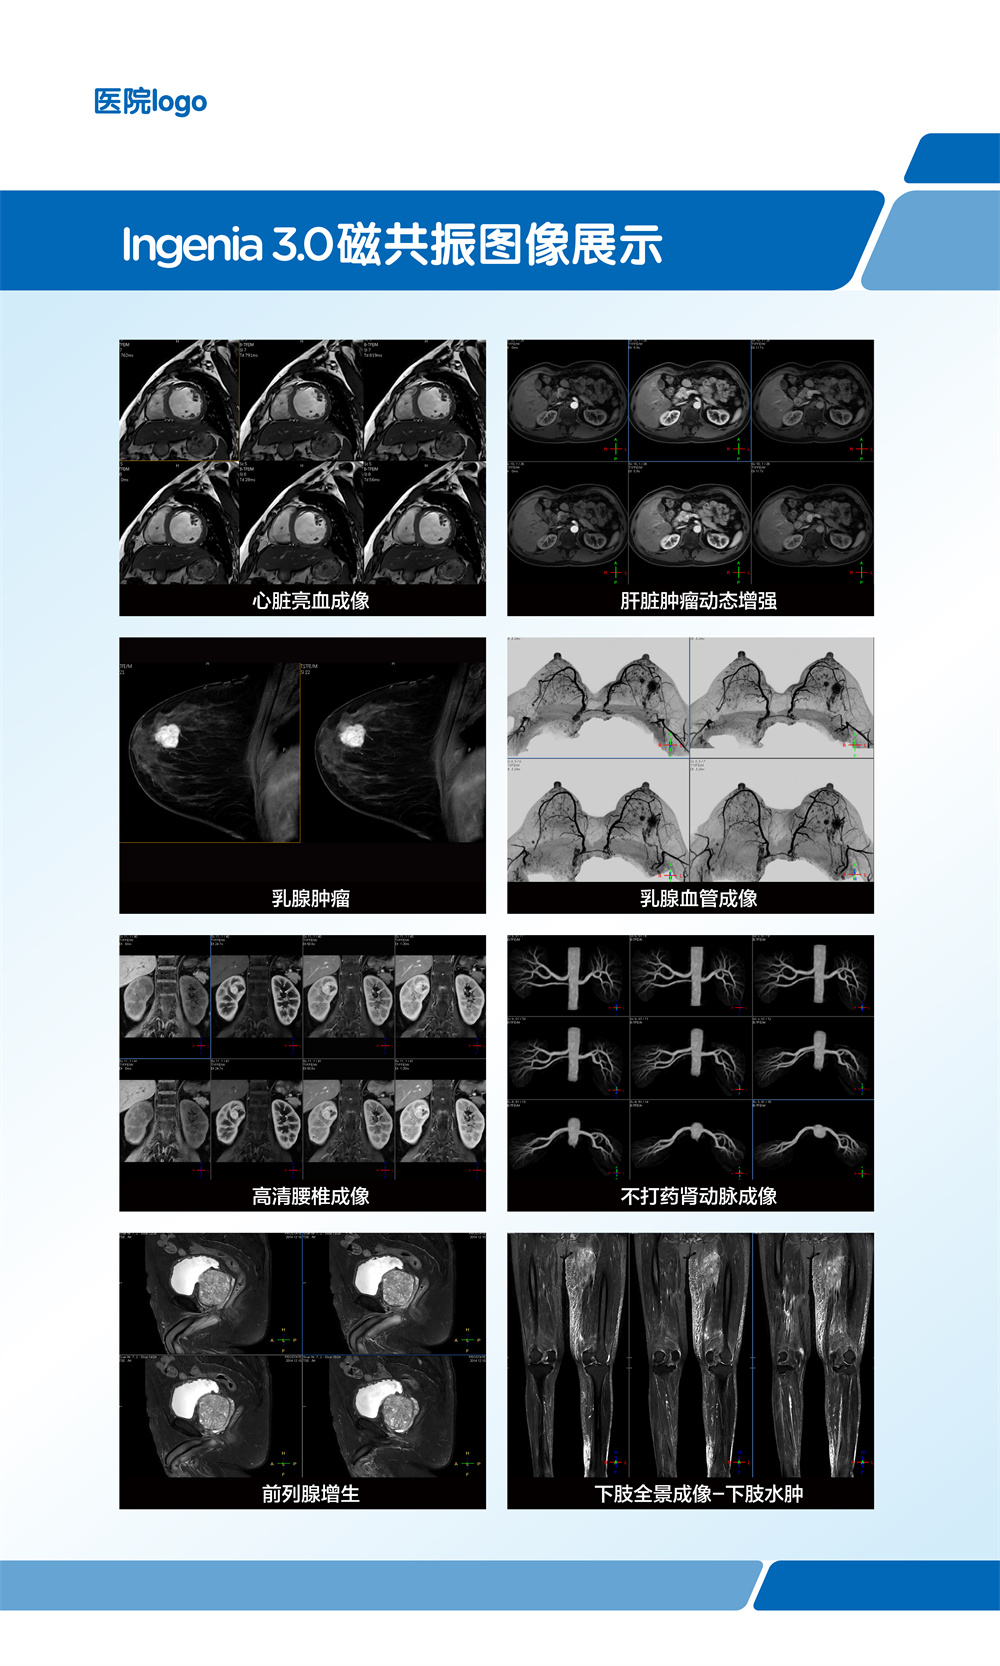

飞利浦大孔径光速Ingenia 3.0T磁共振是业内唯一同时具备"全数字高清成像平台和四维多源射频发射成像平台"的高端3T磁共振,具有病人检查舒适,扫描速度快,图像分辨率高的特点。在神经系统,骨肌系统,体部系统包括心脏和腹部等都有良好的应用和独到优势,为疾病的诊断及治疗提供更可靠、更丰富的信息,对于脑卒中和胸痛等中心的建设起到重要的作用。设备具备飞利浦独有的全数字线圈,可以实现三维全心不打药冠脉成像,无电离辐射和造影剂过敏风险,精准显示冠脉狭窄,有效排查临床无意义的冠脉狭窄(准确度达90%)。

磁共振冠状动脉检查无辐射,无需对比剂,对于缺血性心脏病,可以一次成像完整显示全心冠脉,便于直观诊断冠脉各分支情况。

在全身弥散加权成像的同时,可进行磁共振全身扫描,增加肿瘤检出敏感性。

临床应用范围:寻找恶性肿瘤原发灶;恶性肿瘤分期;全身转移灶筛查;淋巴结转移筛查;术后放化疗疗效监测;恶性血液肿瘤疗效观察;体检与肿瘤筛查。

亮血:血管狭窄筛查。黑血:血管壁斑块成像。

第三代无损加速磁共振成像-压缩感知(CS-SENSE),最快 32 倍加速,已将绝大部分临床成像转化为快速高清容积扫描。